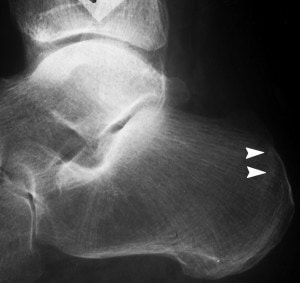

Many people with heel pain may have a bone spur present under the heel, but this is rarely the cause of the pain, or more likely to be a result of the condition.

The most common cause for heel pain is plantar fasciitis, an inflammation of a band of tissue (the plantar fascia) within the arch of the foot that inserts into the heel bone. This commonly causes pain when getting out of bed in the morning, and may recur through the day. Often patients described the feeling of a ‘stone bruise’ under the heel. The treatment of plantar fasciitis can involve the use of taping, stretching, anti-inflammatory medication, foot orthoses and ultrasound (shockwave) therapy.